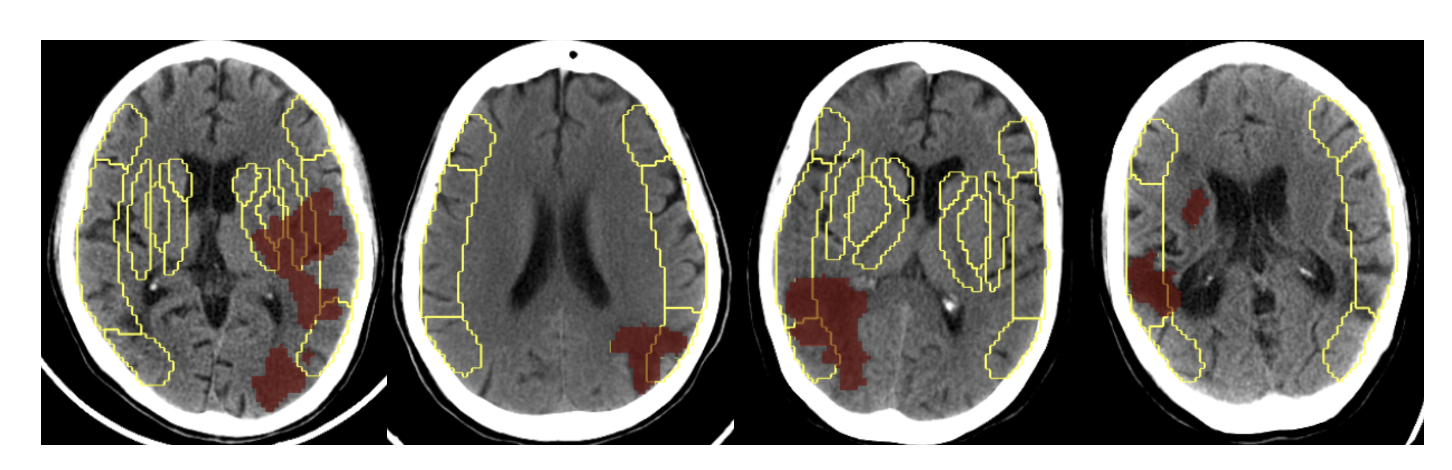

Deep-ASPECTS Deep-ASPECTS: A Segmentation-Assisted Model for Stroke Severity Measurement

Ujjwal Upadhyay, Mukul Ranjan, et al.

ECCV, 2022

arXiv

Deep-ASPECTS is an automated ASPECT scoring system achieving radiologist-level performance, now deployed in hospitals worldwide.